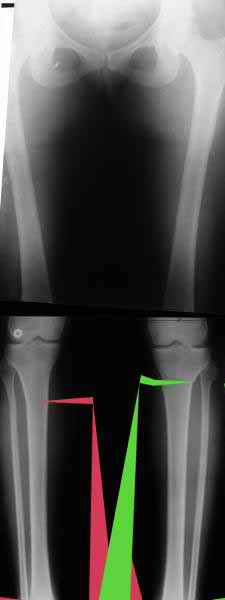

AVM> Александр, а не могли бы вы представить ваши схемы расчета? С учетом

Вот, с учетом и без учета, и на разных уровнях...

Саша Артемьев, может, для данного случая свой вариант нарисуешь?